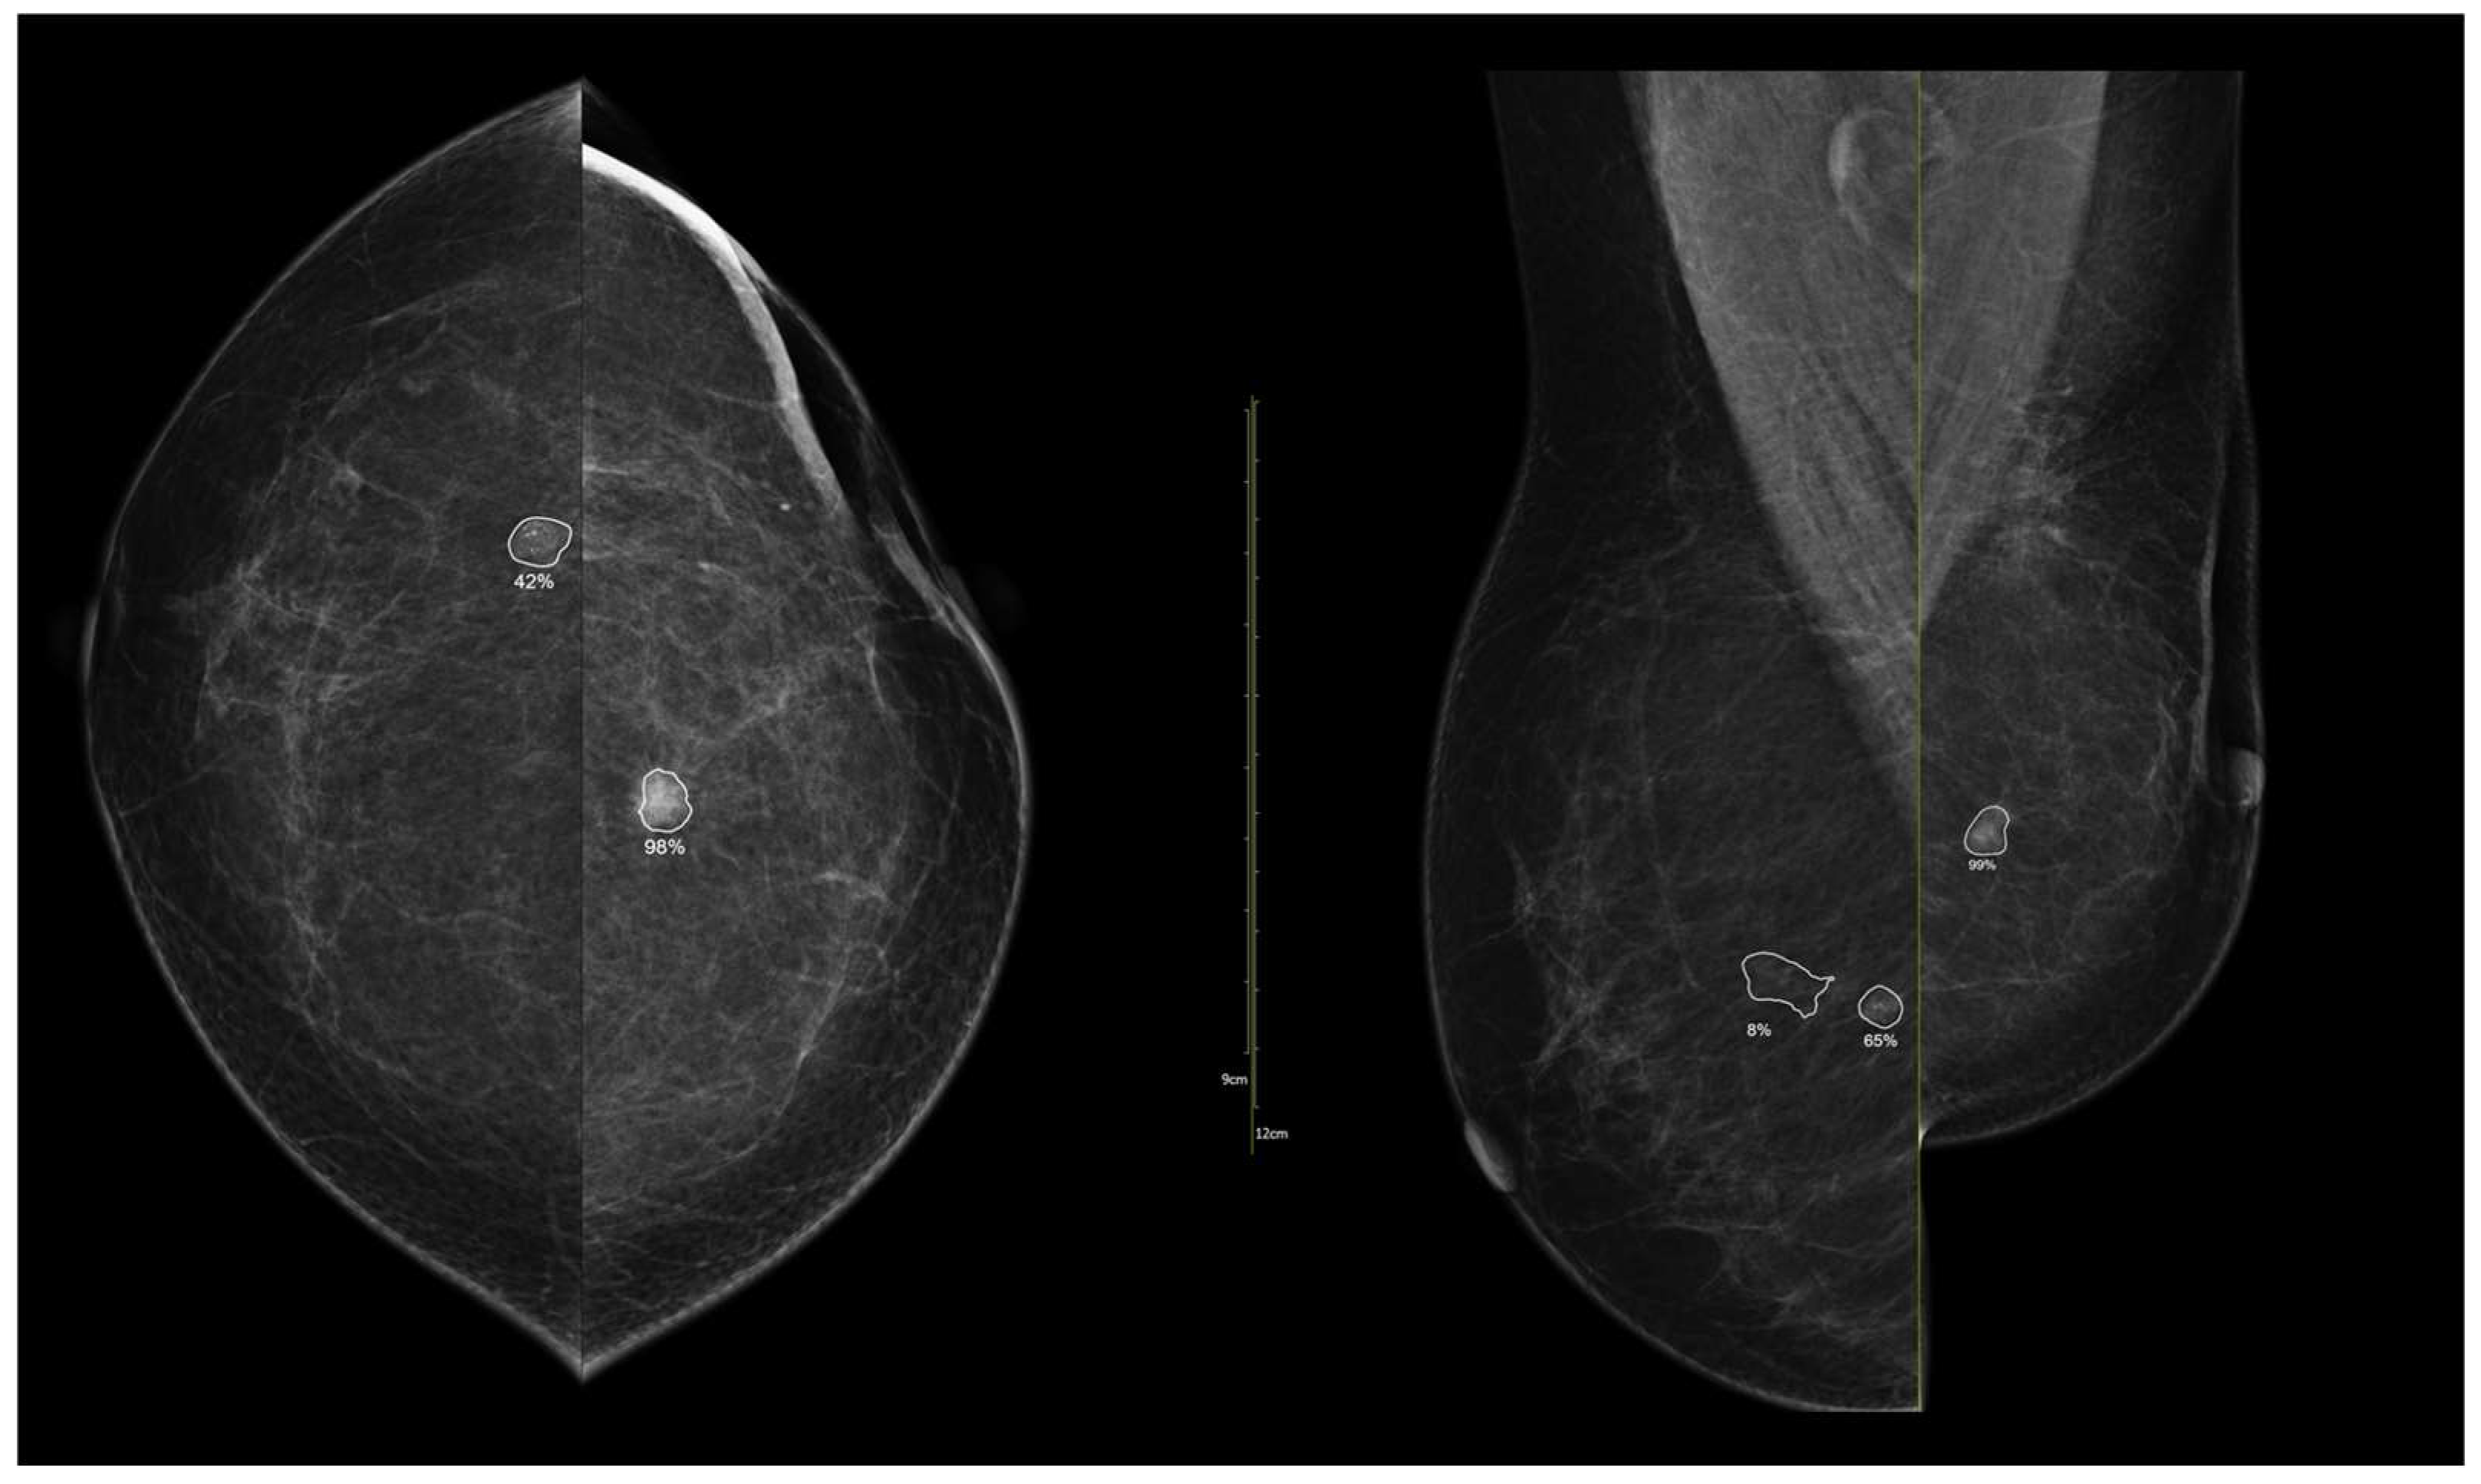

To illustrate the behavior of the iCAD ProFound AI® system across different biological phenotypes, Figure 9 and Figure 10 present representative examples corresponding to Group 1 (luminal) and Group 2 (HER2-positive/triple-negative) tumors. In both cases, the algorithm correctly identified the lesion with high confidence and localized regions corresponding to malignant radiomic traits. These findings should be interpreted in the context of case-level AI assessment rather than lesion-specific prediction.

Figure 9. Example of iCAD ProFound AI® output for a luminal A carcinoma. The lesion detected on the low-energy image is automatically outlined by the AI system with an assigned malignancy probability. The outline shows the regions of highest AI attention, corresponding to irregular shape and spiculated margins, typical of luminal tumors.